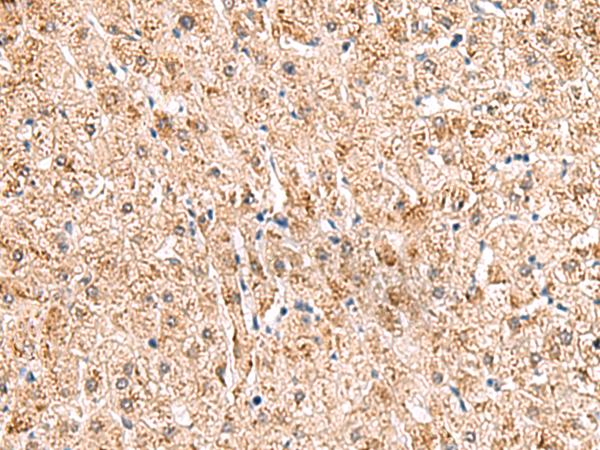

分类: 科研抗体货号: P10075别名: MLS; CCHL; MCOPS7; LSDMCA1应用: WB,IHC反应种属: Human, Mouse